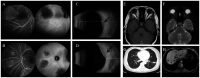

Lung adenocarcinoma with initial binocular symptoms